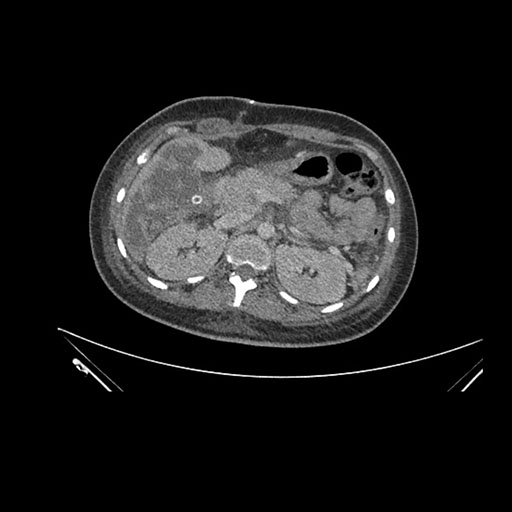

Axial Arterial

Axial Venous